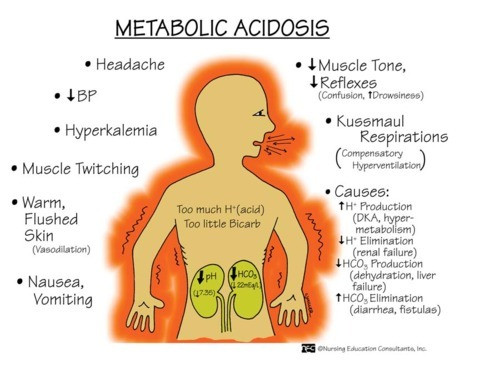

Natrium bikarbonat digunakan untuk mengobati kondisi asidosis metabolik dan dispepsia.